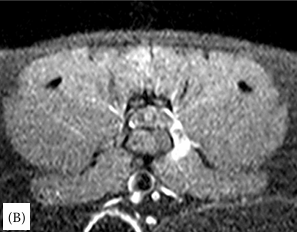

연구 대상은 4세 장모 고양이로 갑작스러운 좌측 후지 절뚝거림과 점프 회피 증상을 보였다. MRI 검사 결과, L6–L7 추간판이 원외측으로 탈출해 신경근을 압박하고, 국소 염증을 동반한 사실이 밝혀졌다. 이는 지금까지 개에서만 드물게 보고된 질환으로 고양이에서는 최초 사례다.